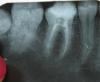

x3m Опубликовано 27 сентября, 2013 Поделиться Опубликовано 27 сентября, 2013 посмеялись - это даже прекрасно.Анютка, не обижайтесь. Ответы даны в стиле заданного вопроса давайте смотреть.красные линии - дно полости зуба, зеленые - периодонт.что смущает?боковой апекс?чуть овер?близость обтурации по малой кривизне в мезиальных?или то, что обведено кружочками? Погадали на прикрепленном снимке Ссылка на комментарий

anytka Опубликовано 27 сентября, 2013 Автор Поделиться Опубликовано 27 сентября, 2013 Я перепломбировывала каналы они были не допломбированы, и очень боялась сделать перфорацию. За время декретного отпуска как то подрастеряла навыки, как будто в первый раз зубы увидила а что в дистальном корне это не перфорация....это верхушка..я конечно извеняюсь но мне нужна ваша помощь... Посмеялись, это хорошо. Все же вопрос к топикстартеру - где именно вы подозреваете перфорацию? Ссылка на комментарий

x3m Опубликовано 27 сентября, 2013 Поделиться Опубликовано 27 сентября, 2013 а что в дистальном корне это не перфорация....это верхушка.Вы спрашиваете или утверждаете? если спрашиваете - да, верхушка. силер продавился.Думаю, при всем желании Вы не смогли бы так перфорнуть под 90 градусов 1 Ссылка на комментарий

M@estro Опубликовано 27 сентября, 2013 Поделиться Опубликовано 27 сентября, 2013 но я просила указать на не достатки моей работы, а не маникюр..... . Из объективного - корневые каналы запакованы неплотно. Коффердама нет ? Хлоркой каналы моете ? Снимок через год покажите нам,будем ошибки с Вами придумывать и исправлять. Ссылка на комментарий